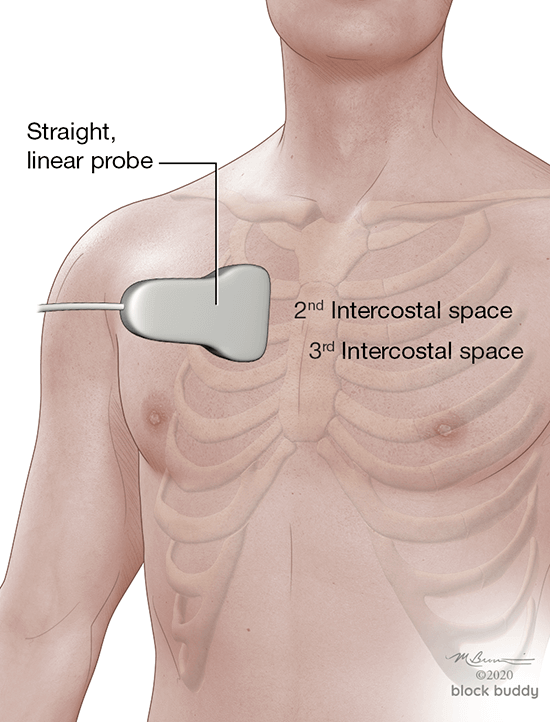

4. Positioning and Scanning

- Scanning can be performed with the patient in a supine, lateral or sitting position.

- In the critically ill patient, perform the scan with the patient supine and modified lateral position.

- When evaluating for a pneumothorax, perform the scan with the patient in the supine or semi-recumbent position.

- Use the anterior axillary (AAL) and posterior axillary (PAL) lines to divide each hemithorax into an anterior, lateral, and posterior zone.

- Further divide each zone into a superior and inferior region by drawing an imaginary horizontal line.

- This will create 6 zones over each hemithorax.

- Initially place the transducer in the long axis over zone 1.

- Reposition the transducer over each subsequent zone to complete the evaluation.

Pneumothorax

- Scan the patient in a supine or semi-recumbent position.

- The transducer is positioned in the long axis over the most anterior aspect of the chest.